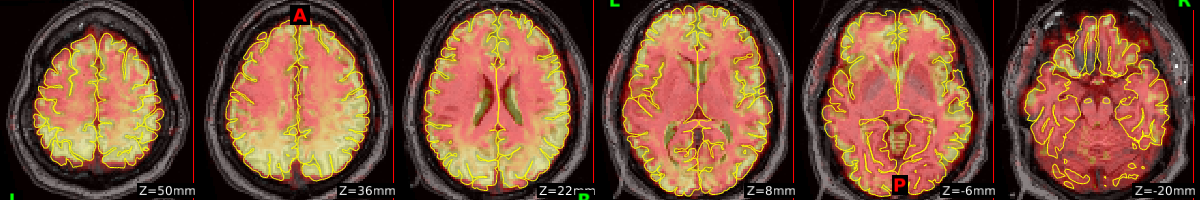

Pial Surface Overlayed on Mean Functional Image (Axial View)

sub-50004_rest

sub-50005_rest

sub-50006_rest

sub-50007_rest

sub-50008_rest